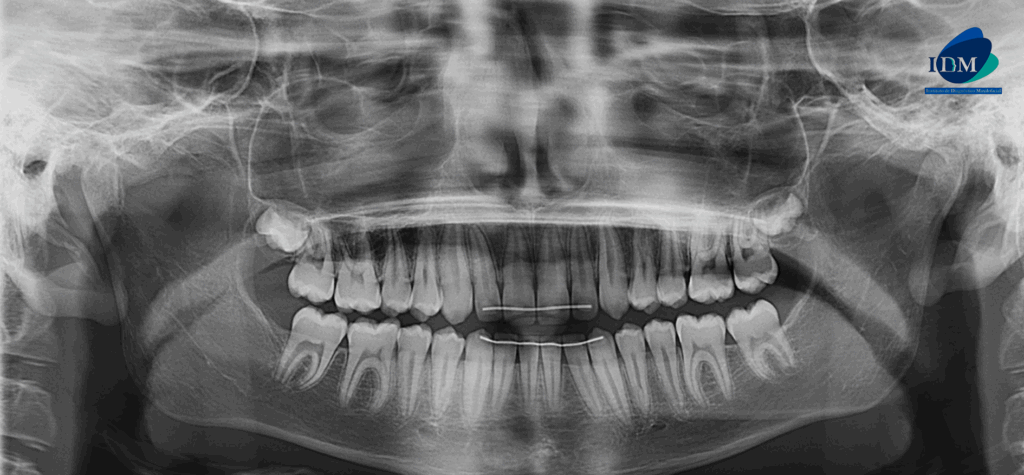

En la radiografía panorámica (Figura 1), se aprecia bifurcación del conducto dentario inferior a nivel distal de pieza 47.

Radiografia Panorámica